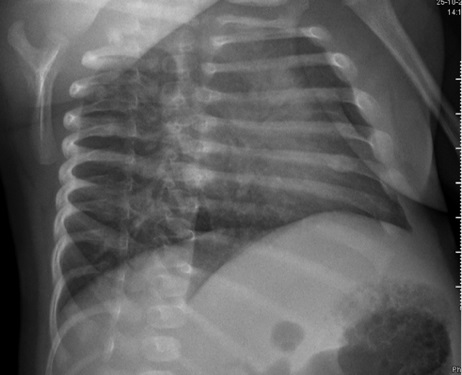

Lactante de 39 días de vida que acude a urgencias por episodio breve resuelto inexplicado, los padres refieren hipotonía e hiporreactividad durante unos minutos en domicilio, recuperándose tras estimulación. Como antecedentes procede de una gestación gemelar, parto a las 34 semanas mediante cesárea por bradicardia fetal sin precisar reanimación. Durante el ingreso en planta presenta dos crisis clónicas de hemicuerpo izquierdo que ceden tras administración de fenobarbital, tras lo cual se inicia monitorización con electroencefalograma de amplitud integrada objetivando nuevos episodios. Se realiza resonancia magnética cerebral, donde se evidencian múltiples focos de sangrado intracraneal y áreas de daño hipóxico-isquémico que sugieren posible trauma no accidental (Figura 1). Posteriormente, se realiza fondo de ojo con hemorragias retinianas y serie ósea con fracturas en diferentes estadios (Figura 2). Dada la situación clínica y la alta sospecha de maltrato infantil se contacta con el juzgado de guardia para valoración del menor. Tras un primer estudio se recomienda ingreso por motivo social de los dos hermanos del paciente, encontrando hallazgos sugestivos de maltrato en una de ellas. Teniendo en cuenta lo anterior, se declara a los menores en situación de desamparo, asumiéndose la tutela de los mismos por parte del Servicio de Menores.

Figura 2. Callo de fractura en el borde lateral del 6º arco costal izquierdo